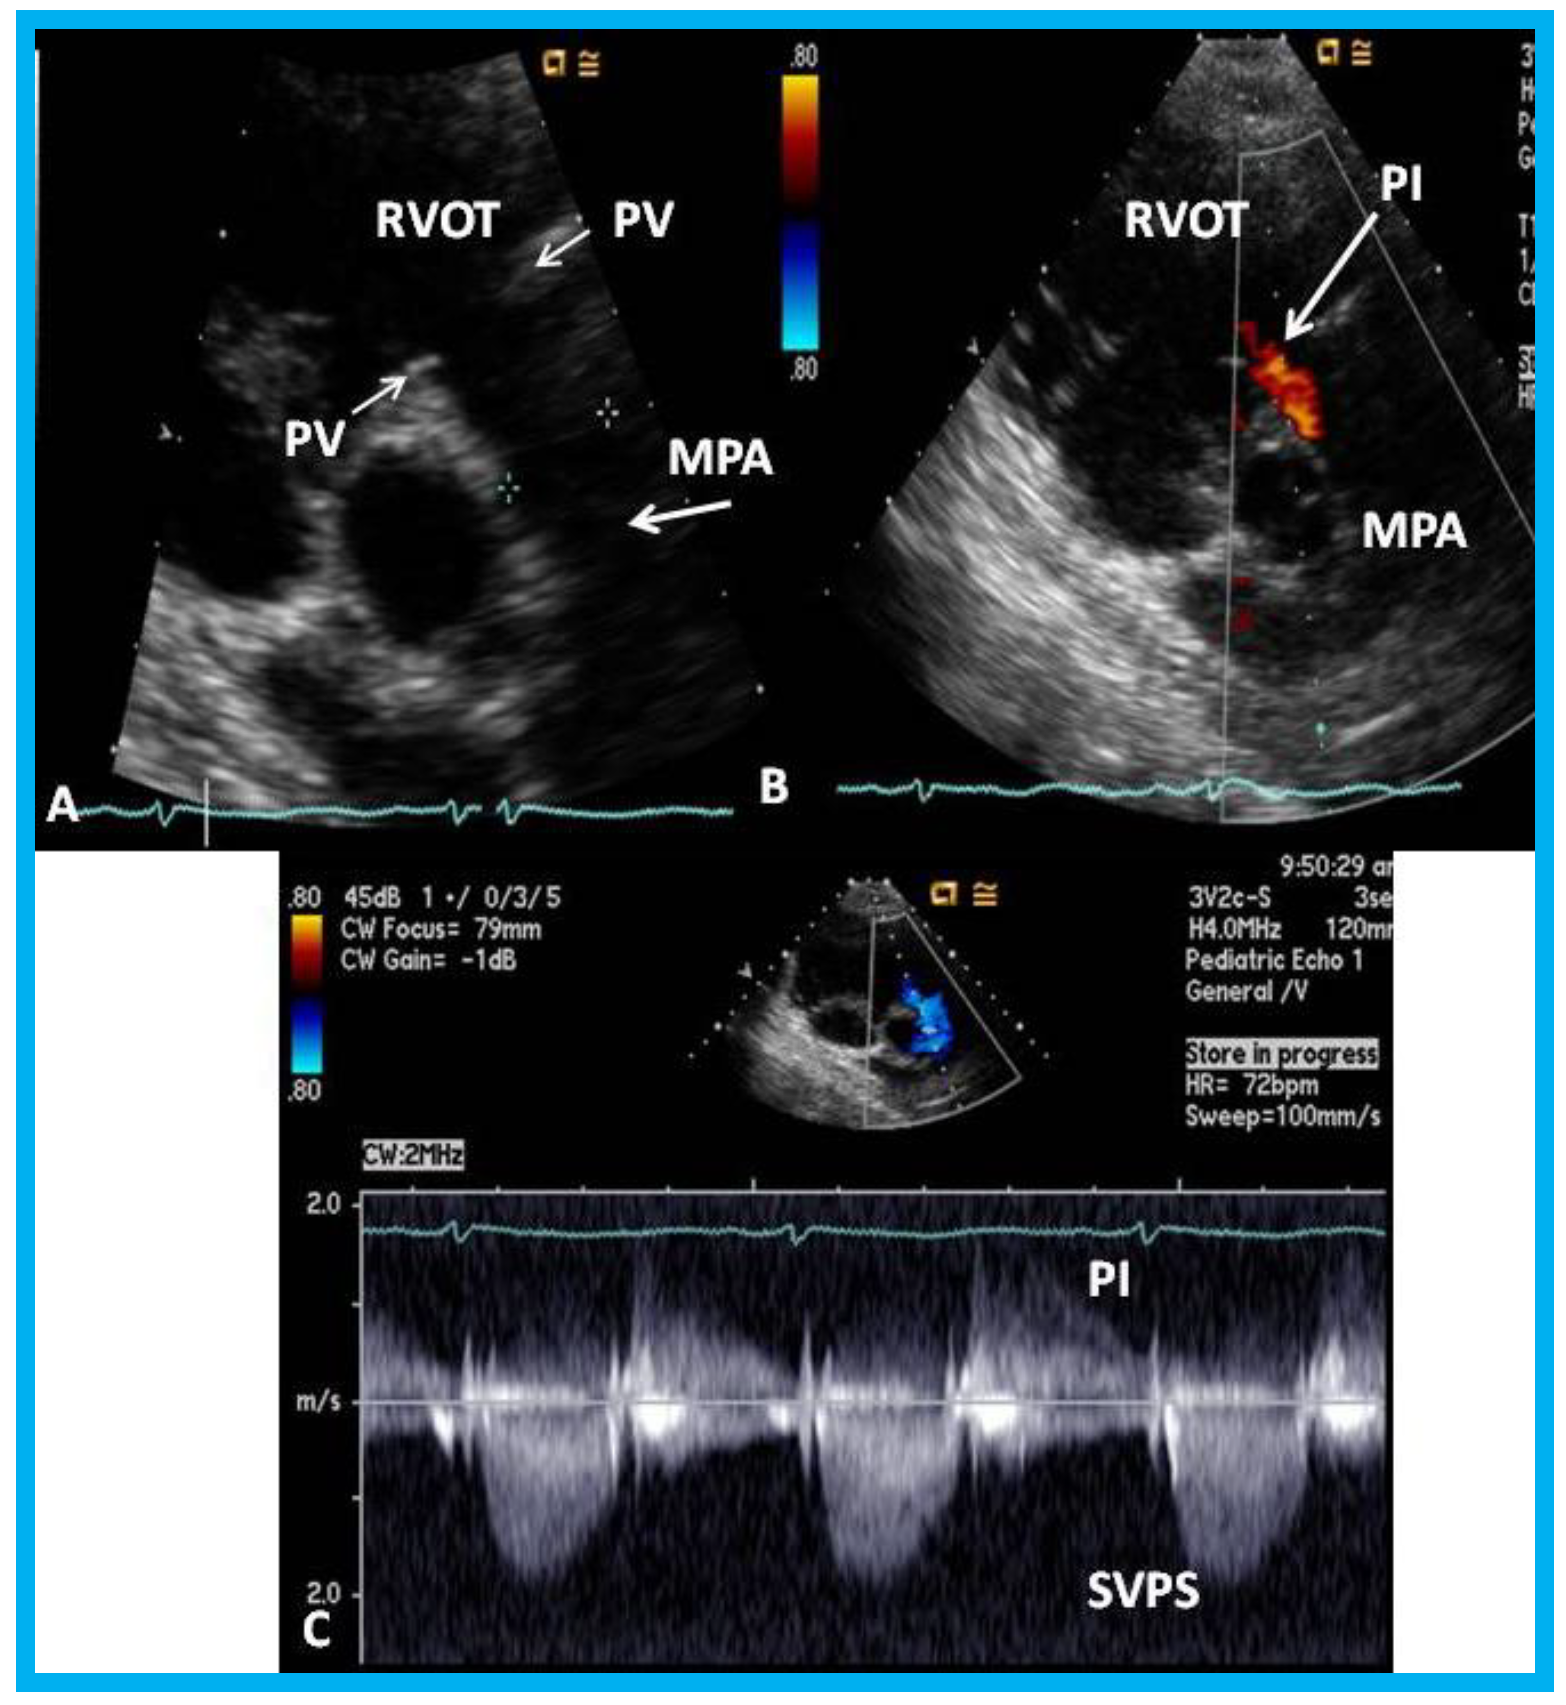

An eleven-year-old female patient had a Nuss procedure for treatment of pectus excavatum [30]. A cardiac murmur was heard shortly before the planned Nuss bar removal at the age of thirteen years. Echocardiographic evaluation revealed external compression (Figure 21), causing supravalvar pulmonary stenosis [31]. Removal of the Nuss bar was performed which documented improvement on echo-Doppler studies (Figure 22). Usefulness of echo studies in evaluation of such issues was emphasized.

Figure 21. (A) Selected video frame from a parasternal short axis view showing echo dense structures (thick blue arrows) within and outside the main pulmonary artery (MPA): Pulmonary valve (PV) leaflets (small arrows) are shown and appear normal. The right ventricular outflow tract (RVOT) and proximal MPA are free of any echo-dense structures. (B) Color-Doppler mapping of the same structures as in panel A shows normal laminar (L) flow in the RVOT and proximal MPA and turbulent (T) flow starting in the proximal MPA, indicating obstruction. (C) Pulse Doppler sampling from the proximal MPA, which shows normal flow velocity. (D) Continuous wave Doppler sampling demonstrating high velocity flow across the MPA with a calculated peak instantaneous gradient of 93.7 mmHg and a mean gradient of 56 mmHg, indicating severe obstruction. Reproduced from Mazur L., et al. [31].

Figure 22. Echo-Doppler studies performed five months after removal of the Nuss bar: (A) Selected video frame from a parasternal short axis view demonstrating no echo dense structures in the right ventricular outflow tract (RVOT) and main pulmonary artery (MPA) that was seen prior to removal of the Nuss bar (Figure 20A). Pulmonary valve (PV) leaflets (arrows) are shown. (B) Color-Doppler mapping of the same structures as in panel A shows mild pulmonary insufficiency (PI) (arrow). (C) Continuous wave Doppler sampling demonstrating low Doppler flow velocity across the MPA with a calculated peak instantaneous gradient of 15 mmHg, indicating minimal supravalvular pulmonary stenosis (SVPS) and mild pulmonary insufficiency (PI). Reproduced from Mazur L., et al. [31].